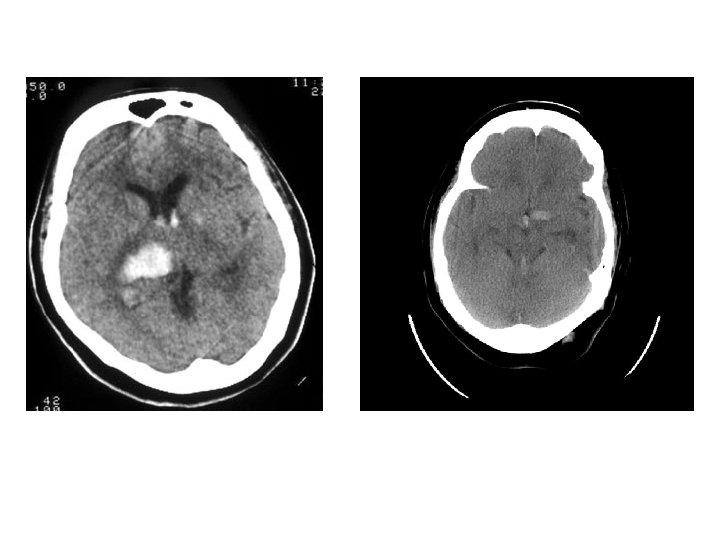

被殼出血 • • Flaccid hemiplegia Complete hemisensory deficit Homonymous hemianopsia Paralysis of conjugate gaze to the side opposite the lesion • Mild to moderate impairment of consciousness with or without headache and vomiting • Neuropsychological disorders (in some cases).

視丘出血 • similar syndromes may occur, but sensory deficit usually predominates over the other manifestations • Oculomotor signs such as forced downward gaze, convergence paralysis, and unreactive miotic pupils. • 被殼出血很大時,可以考慮手術,而視丘出血則 常常往下犯到腦幹,預後相當不好。一般比較不 考慮開刀。 • 另外,視丘非常靠近第三腦室。大部分的視丘出 血都會破到腦室裡面。這點比被殼出血常見。